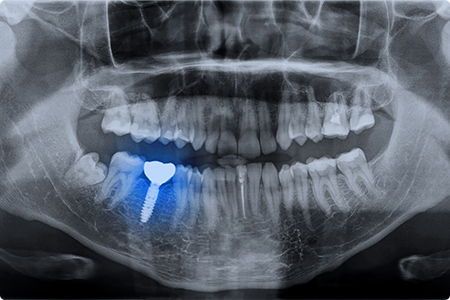

インプラント治療後は定期的なメンテナンスが欠かせません。インプラントはむし歯にはなりませんが、歯ぐきや骨に炎症を起こす可能性があり、歯科医院での定期的なチェックとクリーニング、ご自宅での丁寧な口腔ケアが重要です。3~6ヵ月ごとの検診と毎日のケアの継続で、インプラントを長く快適に使い続けられます。

インプラント周囲炎とは、インプラントの周りに生じる歯ぐきや骨の炎症です。歯垢に含まれる細菌が原因で、歯ぐきが赤く腫れたり、出血したりします。インプラントには歯を守る機能がないため、天然歯より悪化しやすく、進行するとインプラントを支える顎の骨が溶けて、インプラントが抜けてしまうことがあります。